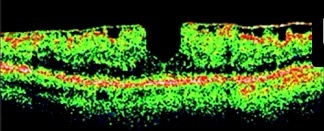

O que é o Pseudo-buraco de Mácula?

Distorção da região foveal, causada por uma MER, que gera impressão de um Buraco de Mácula, porém, sem acometer a espessura total da retina.